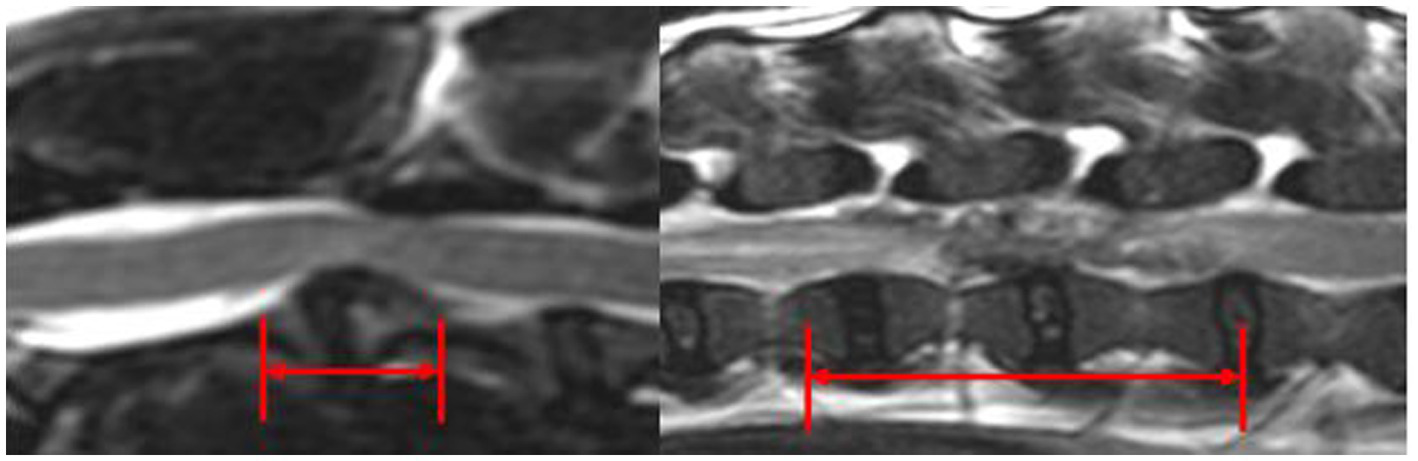

Extruded IVDM was hypointense in T2w images in 11/11 C-IVDE and in 2/28 (7.1%) TL-IVDE, hypointense in T1w images in 10/11 C-IVDE (90.9%) and in 1/28 TL-IVDE (3.6%), hyperintense in T2w images in 0/11 C-IVDE and in 26/28 TL-IVDE (92.9%) and iso-to-hypointense in T1w images in 1/11 C-IVDE (9.1%) and in 27/28 TL-IVDE (96.4%) (p < 0.001). EIVDM extended ≥2 IVD spaces in 0/11 C-IVDE and in 19/28 TL-IVDE (67.9%) (p < 0.001). The mean longitudinal extent of the EIVDM was 0.9 (range 0.5–1.5) in C-IVDE and was 2.6 (range 0.3–4.6) in TL-IVDE (p < 0.001) (Figure 5).

Figure 5

Mid-sagittal T2w images at the level of C2-C3 IVD (left) and L2-L3 IVD (right). The red arrows evaluate the longitudinal extent of the EIVDM within the vertebral canal.

Significant differences between the characteristics of IVDE in the cervical and thoracolumbar region were observed in the present study. The mean longitudinal extent of EIVDM in C-IVDE (0.9 times the length of C6 vertebra) was significantly shorter than the mean longitudinal extent of EIVDM in TL-IVDE (2.5 times the length of L2 vertebra). Extradural IVDM was therefore significantly less spread throughout the vertebral canal in C-IVDE than in TL-IVDE. The meningovertebral ligament is a ligamentous structure that extends from the ventral external surface of the dura mater to the dorsal aspect of the vertebral bodies and IVDs, forming a continuous attachment (27). In dogs, it is more robust in the cervical portion of the vertebral column, particularly between C3 and C5/C6 vertebrae and is finer and less robust in the thoracolumbar and lumbar regions (27). This anatomic barrier could contribute to avoid dispersion of the EIVDM in C-IVDE compared to TL-IVDE. Another hypothesis is that TL-IVDE occurred in a high energy-high velocity context, more easily tearing the meningovertebral ligament and spreading over multiple IVD spaces. In the present study, almost all C-IVDE (8/11) occurred between C3 and C5/C6 vertebrae and were all localized over the affected IVD space. The more robust meningovertebral ligament in this region could explain the more focal IVDE in the cervical region.